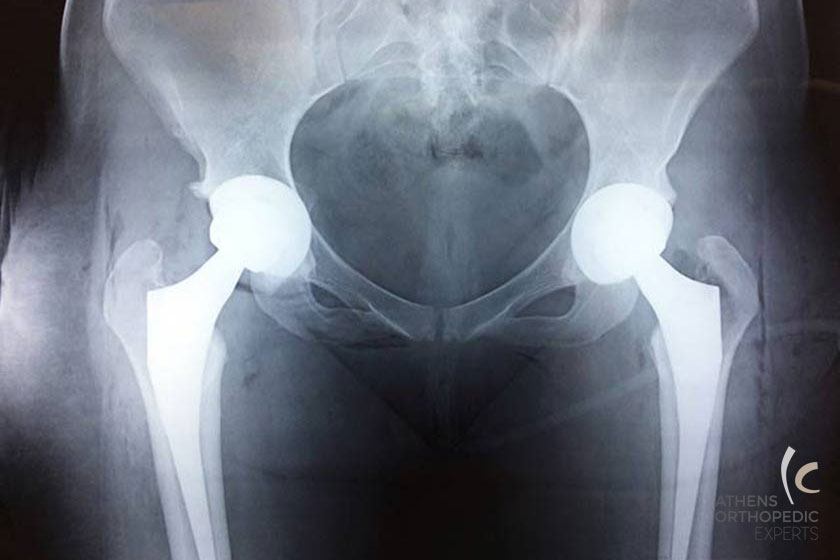

Η ταυτόχρονη ολική αρθροπλαστική και των δυο ισχίων αποτελεί την τελευταία απάντηση ...